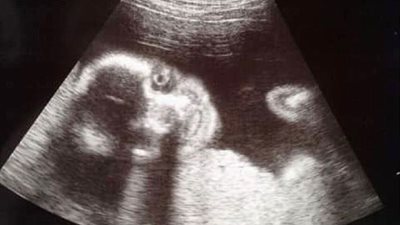

نشرت امرأة صورة أشعة السونار التي ترصد جنينها، بينما يضحك بشكل غريب. وفقا لما نشرته صحيفة "ديلى ميل" البريطانية، نشرت "صوفى ناج" صورة طفلها البالغ من العمر عامين عندما كان جنينا في رحمها وهو يبتسم ...